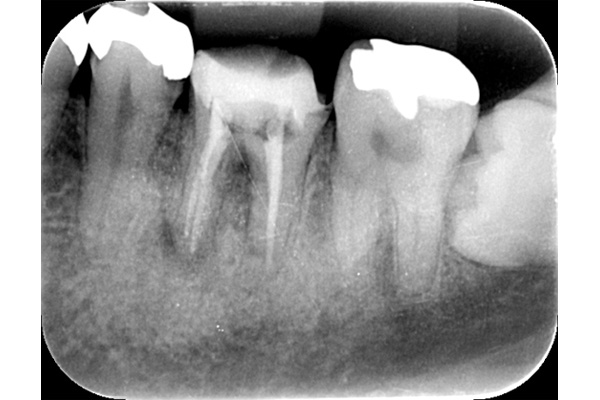

こちらの写真は違和感があるということでレントゲンを撮ったが異常は見つからなかった。しかし、1ヶ月後にもう一度撮影すると、歯が割れているのがわかりました。また、歯の周りの骨の部分がやや黒くなっているのも分かります。